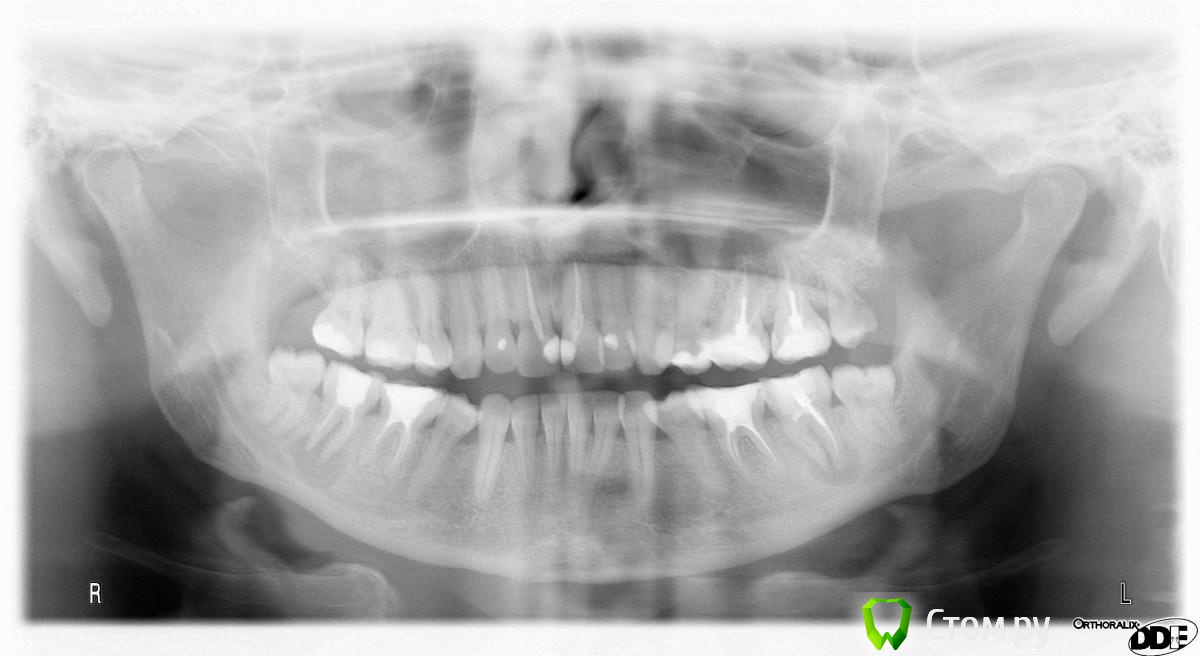

Л Ю С Я Опубликовано 10 января, 2014 Поделиться Опубликовано 10 января, 2014 .Новый кейс-совсем свежий пока без долгосрочного результата.Пациентка попала случайно удаляла зуб 28 и хирург сделал ОПТГ,где стали видны обширные периапикальные процессы в области 37 47.Побывав у меня на консультации и услышав план лечения и стоимость,пациентка решила видимо полечить подешевле.,побывав на консультациях в нескольких клиниках и в итоге даже попала к главному стоматологу нашей области. Все ей сказали что удаление онли. Вернулась,-засада была в том что план я писал исходя из ОТПГ не сделав прицел(виноват),сделав прицел понимаю что все сложнее чем я думал-ну что же тем интереснее.Переписав план лечения и подняв ценник на 40%(пациентке не оставалась выбора),начали лечение.1-посещение-ревизия пломбы.понимаю что кто то до меня с маниакальным упорством пытался запломбировать мезиальный язычный канал каналонаполнителями. Убрал два фрагмента из верхней трети мезиального язычного.2-посещение еще фрагмент из мез язычного плюс немного с дистальными поработал(их оказалось два сплит в верхней трети)3-визит обошел фрагмент в мезиальном щечном и доработал остальные каналы.4-визит -паковка.На предпоследнем снимке видны поры-допаковал(просто на финальном не очень видно)Класс! Ждем рекол через 6 месяцев. Паковка чем? Сквирт? Ссылка на комментарий